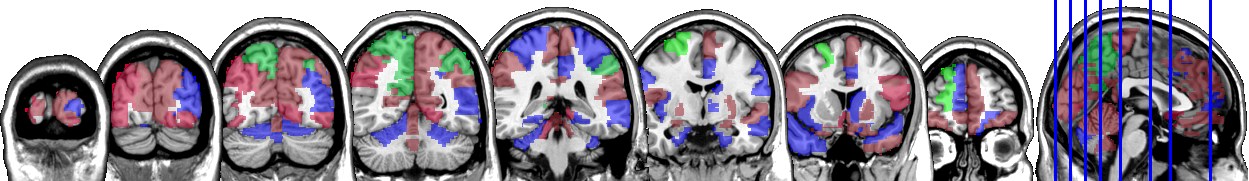

One motivating example for our methods is the application to the functional magnetic resonance imaging (fMRI). The dataset consists of the functional signals of the brain activities measured by blood-oxygen-level-dependent (BOLD), which detects hemodynamic changes based on the metabolic demands followed by neural activities. There are pre-specified regions of the brain, and the BOLD signals associated with multiple voxels in each region are integrated into one signal for that region. Thus, the fMRI data are considered to be multivariate functional data in which each functional predictor represents the signals from a region of the brain. In Section 8, we regress the ADHD index to the regional BOLD activities of the fMRI of the human subjects. There are regions of the brain in the data, and our methods reduce the regions to 41 regions with significantly lower errors than the linear functional regression. Figure 1 displays the regions of the brain’s atlas that are identified by our method. It shows that the methods simplify the data analysis and provide clear representation while keeping the crucial information. The analysis shows that there is an urgent need for new methods in the fields of medical and life sciences as well as other related areas.

In Figure 4 and Figure 5, we display the regions associated with the estimated active sets for IQ and ADHD by the MFG-LASSO respectively. The final active sets of the algorithms were extracted, and matched with the AAL’s atlas where each of the regions has a label. The regions were manually entered into the WFU picked atlas Maldjian and et al. (2003) tool of the SPM-12 ran on MATLAB 2020b to produce mask.nii files. The mask files were imported on MRIcron software to produce the multi-slice images.

The active sets cover the regions associated with IQ in Yoon and et al. (2017) such as cerebello-parietal component and the frontal component. It is mentioned in the paper that the parietal and the frontal regions are strongly associated with intelligence by maintaining a connection with the cerebellum and the temporal regions. The shaded areas cover the ones mentioned in Goriounova and Mansvelder (2019) as well. We provide the name of the regions associated with these active sets in the appendix.

It is interesting that ADHD and IQ have a large proportion of common active sets. For instance, when MFG-LASSO is applied, they overlap in ROIs where the size of active sets are and for IQ and ADHD respectively. On the other hand, the ROIs that are associated with ADHD but not with IQ are the middle and superior frontal, the Parahippocampal, the inferior parietal, and the superior temporal pole gyri. The ratio of the number of right hemisphere regions to the left ones associated with IQ is significantly greater than that of ADHD.